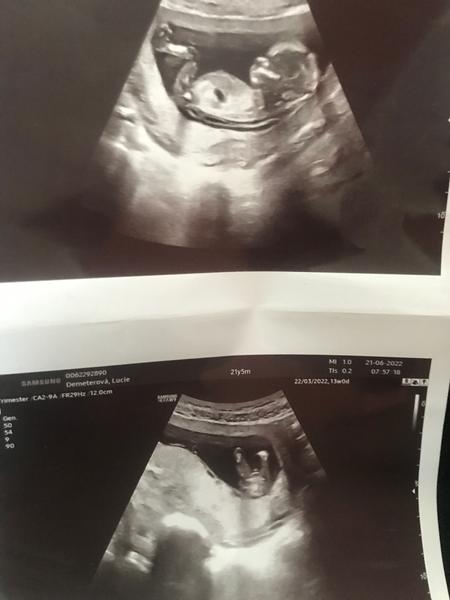

13. týden těhotenství. Lze z těchto fotek určit pohlaví?

Jsem teprve ve 13. tt a moc bych chtěla holčičku, ale myslím si, že je to kluk. Pan doktor mi to teď na prvním screenengu ještě nechtěl říct. Asi si nebyl jistý.🙂